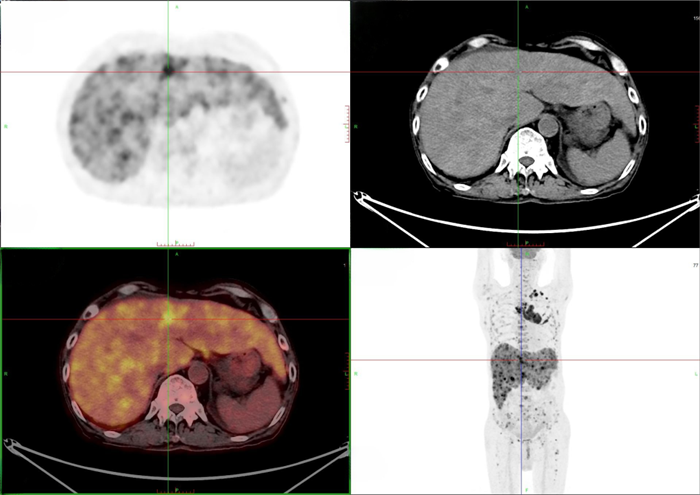

肝臟多發(fā)轉(zhuǎn)移

之后,徐伯伯來到我院進行PET/CT檢查,發(fā)現(xiàn)左肺上葉惡性結(jié)節(jié),為原發(fā)灶,并引起縱隔多發(fā)淋巴結(jié)轉(zhuǎn)移。同時,肝臟、全身多處骨骼、頸部、腹部、腹股溝等多處的淋巴結(jié)出現(xiàn)了遠處轉(zhuǎn)移。